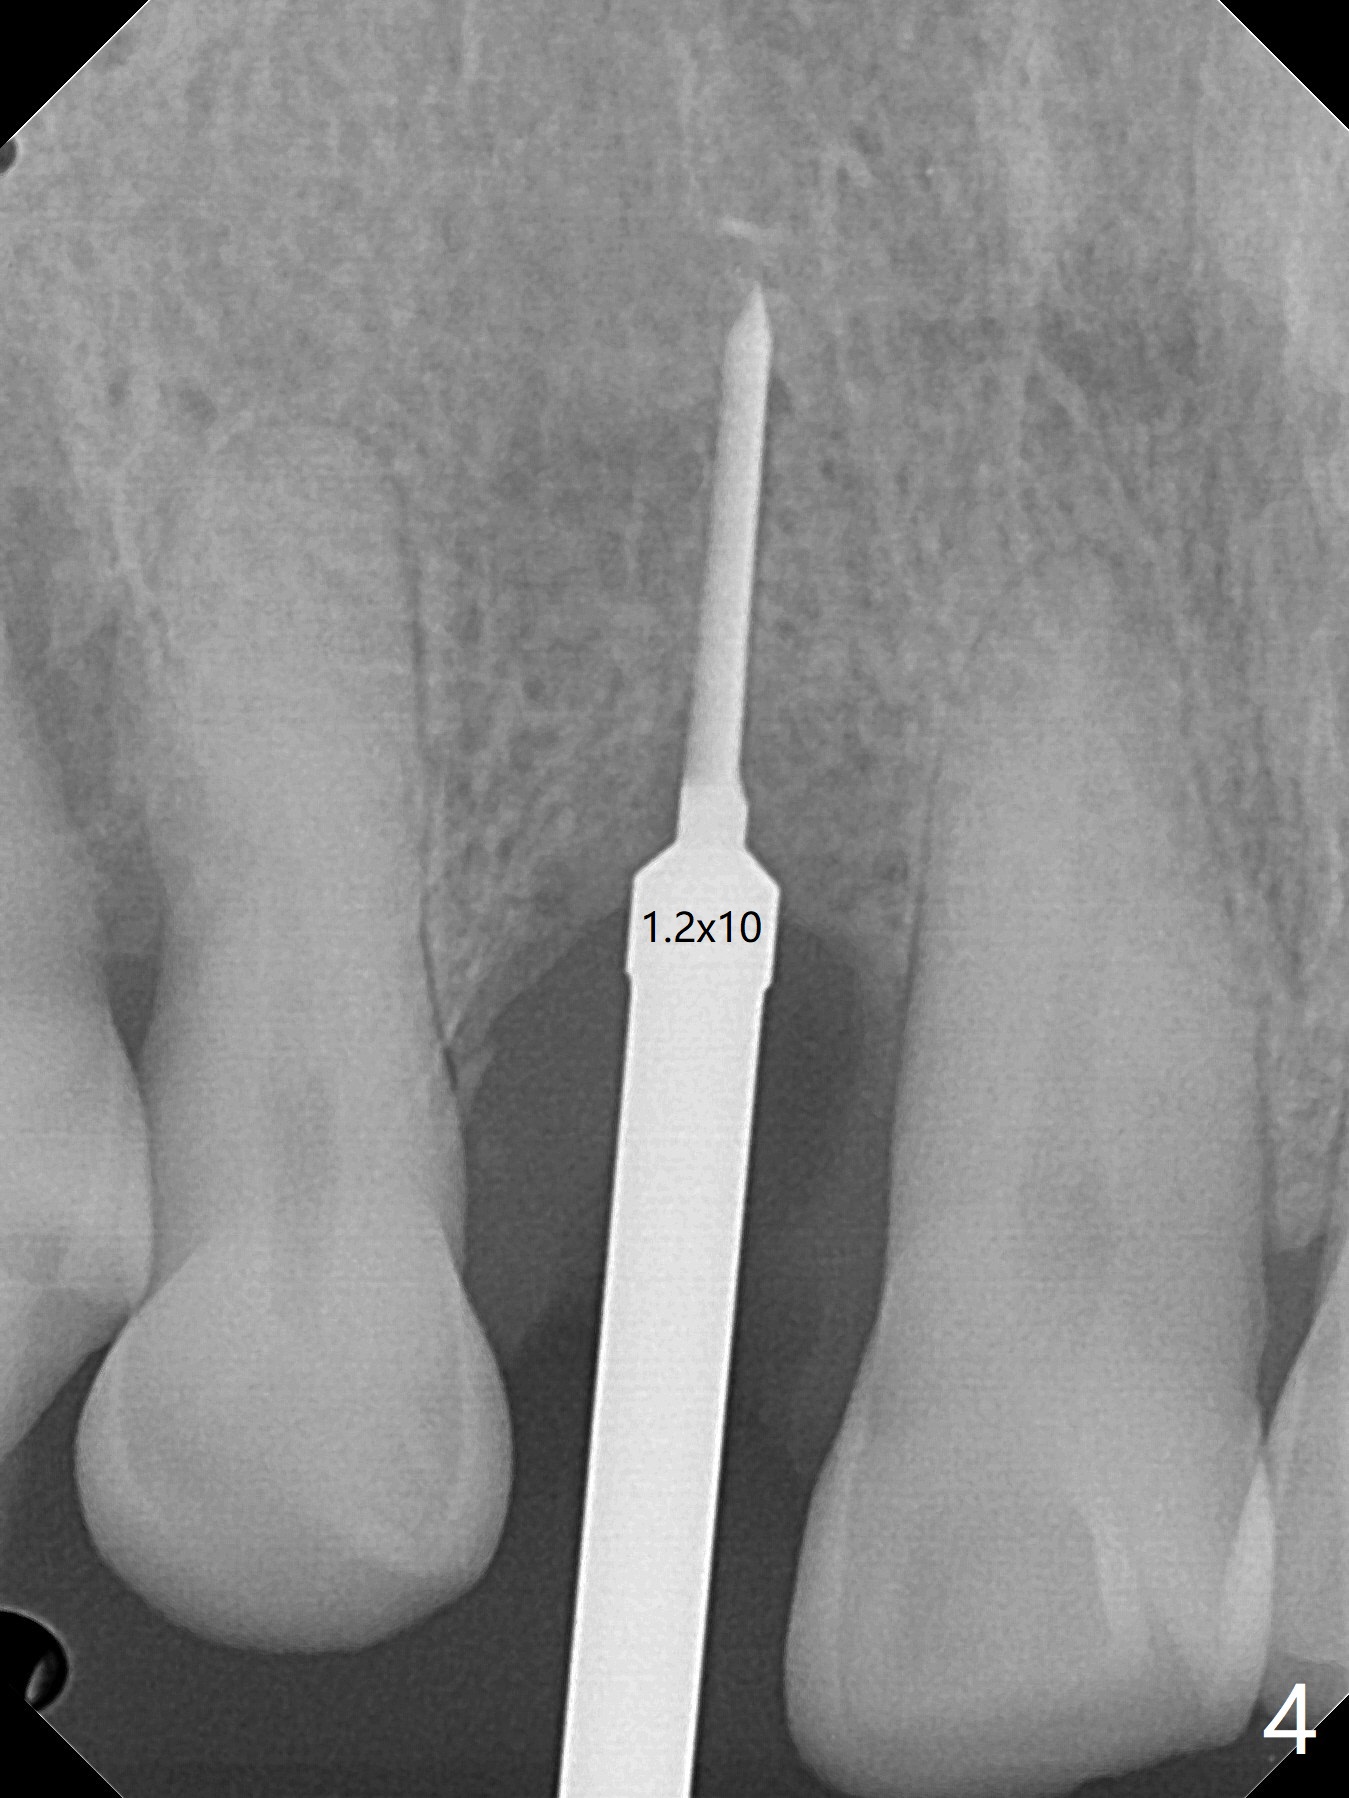

68岁男士右上2严重骨质吸收,颊侧骨板缺失,术前牙龈退缩也十分明显(图一,二),术中对脆弱牙龈缘(图三:*)不应施加任何压力或者牵拉,更不能切开,保持最佳血供。按照术前设计,在牙槽窝腭侧钻洞(图四),植入2.5x15毫米一段式植体(扭力>35Ncm),基台特长(牙龈厚,图五)),基台位于合适修复位置(图六),4-5毫米螺纹颊侧暴露(图七:*)。植骨(图八(CT冠状切面(拔牙后:黑色)):箭头)前,将PRF膜(白线)一头(a)插入牙槽窝颊侧,另外一头(图八,九:b)放置颊侧牙龈颊侧。然后填入粘性骨粉(图九:S;图十四:*),将b头PRF膜往下翻,它末端事先冲一个洞(punch a hole using sterilized rubber dam punch),插入基台(图十(粉红色),十一),这样PRF膜不移位,牢靠地固定骨粉(图十(红圆圈),图十四:*),最后使用树脂敷料覆盖伤口(图十二,十三:A),同样需要基台(箭头,也就是一段式植体)固定,也就是没有即刻植体,就没有骨粉固位。术后两个月伤口缩小,肉芽组织生长(图十五)。撤除树脂敷料后,制作临时牙冠,半个月后唇侧植体有些暴露(图十六),嘱咐强化口腔卫生。